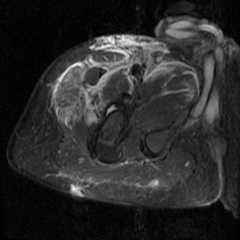

Figure 2a.

Axial STIR images of the right thigh in axial planes demonstrating extensive high signal abnormality in the adductor, anterior, and posterior compartments, representing edema and ischemia from alprazolam microembolism. [Powerpoint Slide]